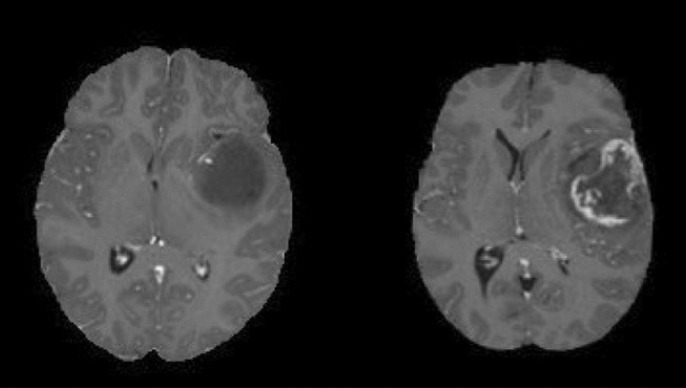

Just a few months ago, Sachin started experiencing severe headaches and weakness in his arms and legs. After tests at Scarborough Health Network, an MRI revealed a devastating diagnosis: a large left cerebellar mass, measuring about 4.5 x 5.5 x 4.4 cm, involving key areas of the brain like the left middle cerebellar peduncle and pons. This tumor is compressing critical structures, including the fourth ventricle and brainstem, causing displacement and mild hydrocephalus (buildup of fluid in the brain). The doctors have described it as an aggressive tumor requiring immediate and intensive treatment, consistent with a high-grade (stage 4) brain tumor.